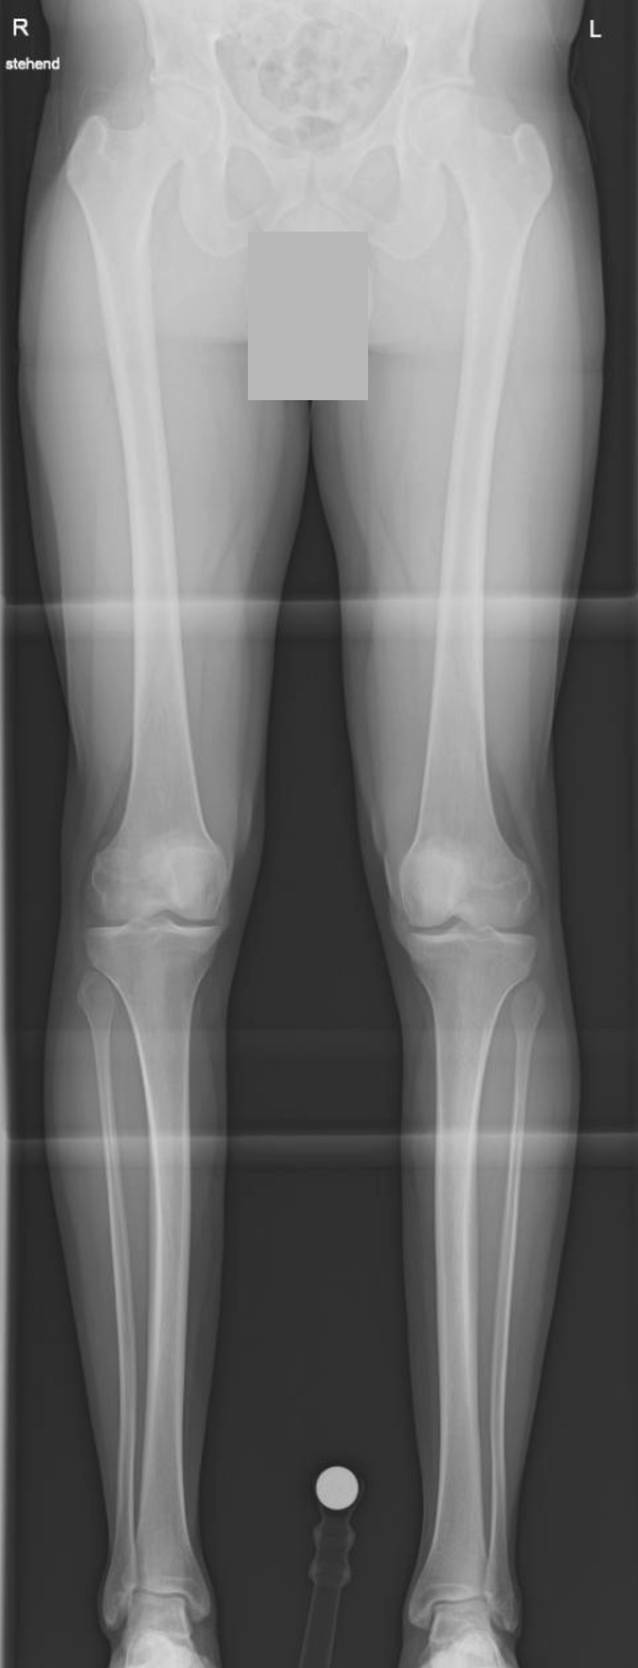

Bei Beschwerdepersistenz trotz mehrmonatiger Physiotherapie erfolgt eine Weiterabklärung der Torsion mittels Torsions-MRT der unteren Extremitäten und eine Röntgen-Ganzbeinaufnahme. In der Torsions-MRT bestätigt sich die erhöhte tibiale Außentorsion mit gemessen 43 und 39° links (Abb. 2). Für die Torsionsmessung wird tibial der Winkel zwischen der Transmalleolarachse direkt oberhalb des oberen Sprunggelenks und der Tangente an die posterioren Tibiakondylen direkt unterhalb der Kniegelenklinie verwendet [31, 36]. Auch bestätigt sich die erhöhte femorale Antetorsion mit rechts 30 und links 34° nach Murphy [27]. Im Ganzbeinbild zeigt sich bei nach innen gerichteter Patella eine gerade Beinachse (Abb. 3). Im „winking sign“ zeigt sich eine Überlagerung der lateralen Femurkondyle mit der lateralen Eminentia tibae, was bei korrekt zentrierter Ganzbeinaufnahme auf eine Torsionspathologie oder erhöhte Knieversion (intraartikuläre femorotibiale Rotation) hinweisen kann [12]. In diesem Fall zeigt sich keine erhöhte Knieversion in der Rotations-MRT, die intraartikuläre femorotibiale Rotation beträgt rechts 2 und links 6° (Norm < 10–15°). Der TT-TG-Abstand („tibial tuberosity – trochlear groove distance“) ist rechts mit 11 mm normwertig und links mit 20 mm grenzwertig erhöht.

Abb. 3

Röntgen-Ganzbeinaufnahme mit nach innen gerichteter Patella, gerade Beinachse. (Mit freundl. Genehmigung, © T. Tondelli et al.)